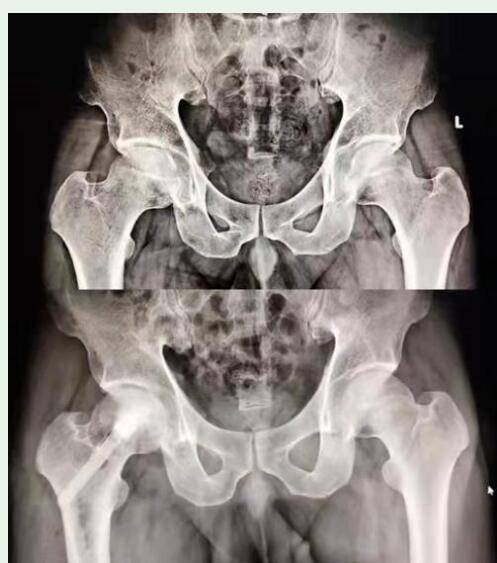

图说:这是本文提及的患者的髋关节正位片,可见双侧股骨头坏死征象明显

改良后外侧保留梨状肌入路微创全髋关节置换一期治疗双侧股骨头坏死